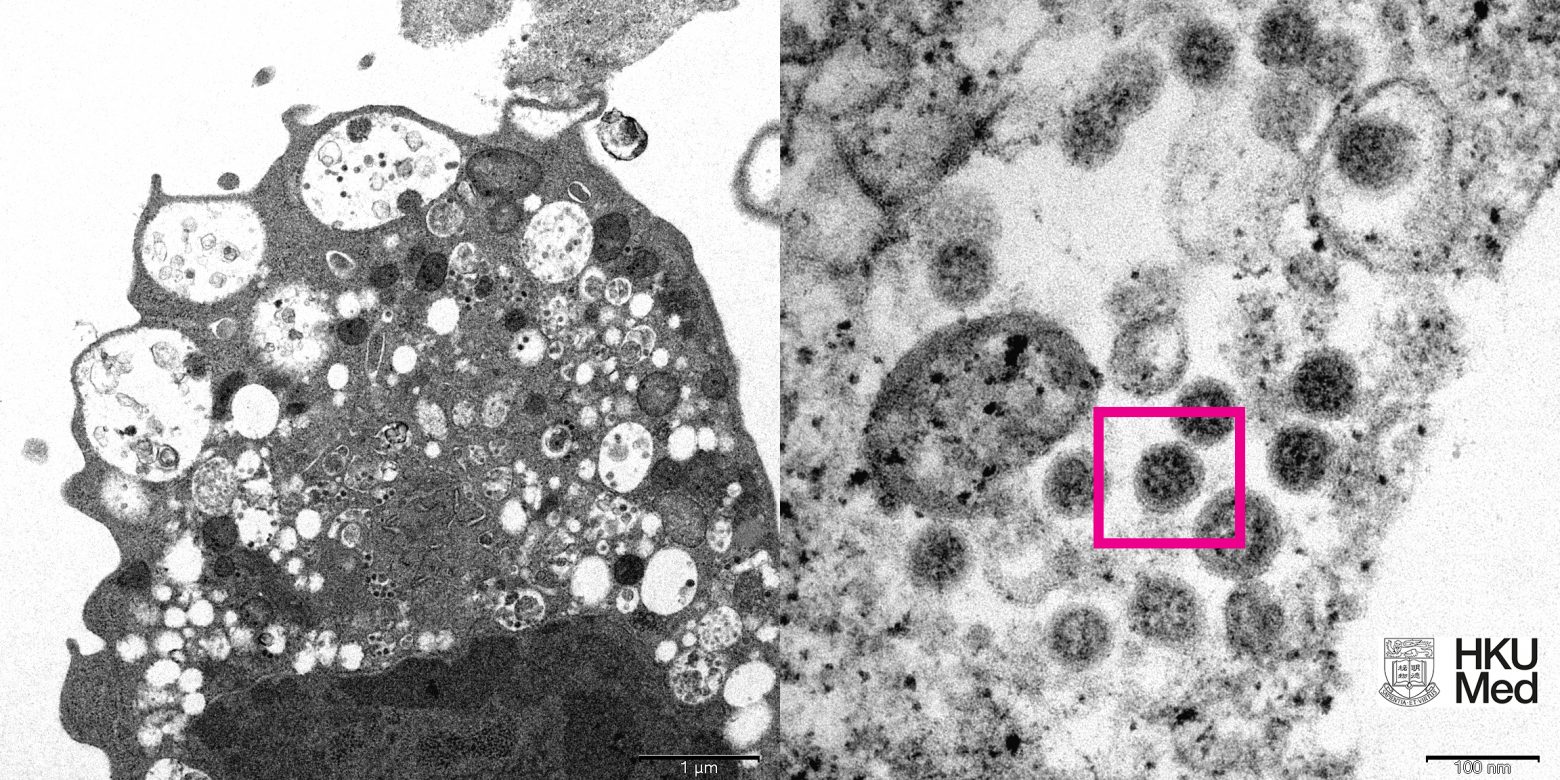

Την εικόνα της Όμικρον, μέσα από ηλεκτρονικό μικροσκόπιο αποκαλύπτει το πανεπιστήμιο του Χονγκ Κονγκ.

Σύμφωνα με το APA, επιστήμονες στον τομέα της υγείας, συμπεριλαμβανομένων παθολόγων και ιολόγων, κατάφεραν να λάβουν μια ηλεκτρονική μικρογραφία ενός κυττάρου (Vero E6) από το νεφρό ενός πιθήκου που μολύνθηκε με το συγκεκριμένο στέλεχος.

Στη συνέχεια το Πανεπιστήμιο δημοσίευσε τις εικόνες χαμηλής και υψηλής μεγέθυνσης.

Photo credit: Professor John Nicholls, Clinical Professor of Department of Pathology; and Professor Malik Peiris, Tam Wah-Ching Professor in Medical Science and Chair Professor of Virology, School of Public Health, HKUMed; and Electron Microscope Unit, HKU.

Αριστερά, είναι η ηλεκτρονική μικρογραφία χαμηλής μεγέθυνσης κυττάρου νεφρού πιθήκου (Vero E6) μετά από μόλυνση με την παραλλαγή Omicron SARS-CoV-2. Δείχνει κυτταρική βλάβη με διογκωμένα κυστίδια που περιέχουν μικρά μαύρα ιικά σωματίδια.

Δεξιά, είναι η ηλεκτρονική μικρογραφία υψηλής μεγέθυνσης μολυσμένου κυττάρου Vero E6. Δείχνει συγκεντρώσεις ιικών σωματιδίων με αιχμές σχήματος κορώνας στην επιφάνειά τους (κόκκινο πλαίσιο).